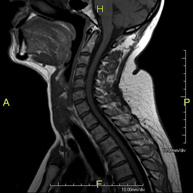

- RM de columna cervical

Prova diagnòstica no invasiva que consisteix en l'obtenció d'imatges d'alta definició anatòmica de la columna cervical mitjançant l'ús d'un camp electromagnètic i ones de ràdio (com un emissor i un receptor). No utilitza radiació ionitzant. Indicacions: traumatisme, degeneració de la columna, hèrnies. - RM de columna dorsal

- RM Columna Cervical

Prova diagnòstica no invasiva que consisteix en l'obtenció d'imatges d'alta definició anatòmica de la columna cervical, mitjançant l'ús d'un camp electromagnètic i ones de ràdio (amb un emissor i un receptor). No utilitza radiació ionitzant. Indicacions: traumatisme, degeneració de la columna i hèrnies. - RM Columna Dorsal